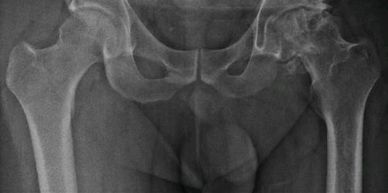

Artroplastía total de cadera bilateral en un tiempo

Paciente de 47 años, con artrosis bilateral de cadera. Se realizó reemplazo articular de ambas caderas en un tiempo con prótesis no cementada total